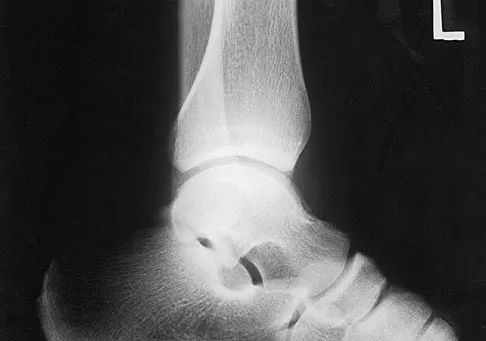

A 42-year-old athletic trainer has a persistent popping sensation about the lateral ankle associated with weakness and pain following a remote injury. Deficiency in what structure directly leads to this pathology?

Explanation

The patient has instability of the peroneal tendon. The superior peroneal retinaculum is the primary retaining structure preventing peroneal subluxation. It is a thickening of fascia that arises off the posterior margin of the distal 1 to 2 cm of the fibula and runs posteriorly to blend with the Achilles tendon sheath. The inferior peroneal retinaculum attaches to the peroneal tubercle of the calcaneus and is not involved in this pathology. A deficient groove in the posterior distal fibula may also be a contributing factor in the development of the condition.